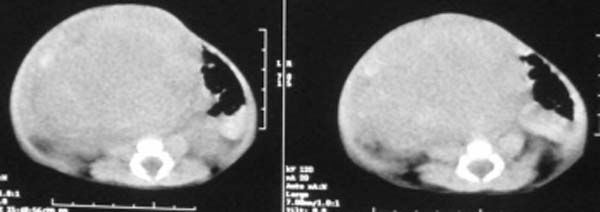

这个女孩刚出生一天,肚子比较大,没任何症状.比较少见,请大家积极发言!!

这个病例定位诊断:1、可以肯定肿块不在肝脏。2、肿块在腹膜后,因为肠管向前侧方推移,肾脏明显向后推挤,腹主动脉及下腔静脉被肿块包绕。

定性诊断比较困难,该病例肿块为实质性,小儿最常见的腹膜后肿瘤第一位应该是-----神经母细胞瘤!

我的意见是-----定位诊断是“1、可以肯定肿块不在肝脏。2、肿块在腹膜后,因为肠管向前侧方推移,肾脏明显向后推挤,腹主动脉及下腔静脉被肿块包绕。”

右中下腹部囊实性密度影,内有小细条状钙化影,胃及腹部肠管受压向左移位,肾脏受压向后移位,腹主动脉及下腔静脉包饶。考虑腹膜后畸胎瘤可能性大。